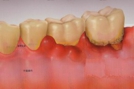

「歯周病」とは、細菌感染によって「歯を支えている顎の骨が溶かされてしまう病気」です

3.歯周外科手術

歯周病の進行が重度の場合、歯を抜かずに残すためには歯茎の手術が必要となることがあります。また、必要によって、前後の歯と固定し、かみ合わせの安定化を図る場合もあります。